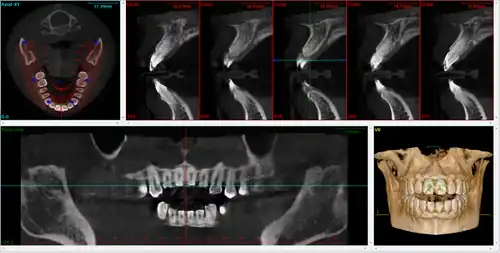

It is possible for both tooth decay and periodontal disease to be missed during a clinical exam, and radiographic evaluation of the dental and periodontal tissues is a critical segment of the comprehensive oral examination. The photographic montage at right depicts a situation in which extensive decay had been overlooked by a number of dentists prior to radiographic evaluation.

Computed tomography

There is increasing use of CT (computed tomography) scans in dentistry, particularly to plan dental implants;[19] there may be significant levels of radiation and potential risk. Specially designed CBCT (cone beam CT) scanners can be used instead, which produce adequate imaging with a stated tenfold reduction in radiation.[20] Although computed tomography offers high quality images and accuracy,[21] the radiation dose of the scans is higher than the other conventional radiography views, and its use should be justified.[22][23] Controversy surrounds the degree of radiation reduction though as the highest quality cone beam scans use radiation doses not dissimilar to modern conventional CT scans.[24]

Cone beam computed tomography

Cone beam computed tomography (CBCT), also known as digital volume tomography (DVT), is a special type of X-ray technology that generates 3D images. In the recent years, CBCT has been developed specifically for its use in the dental and maxillofacial areas[4] to overcome the limitations of 2D imaging such as buccolingual superimposition.[25] It is becoming the imaging modality of choice in certain clinical scenarios although clinical research justifies its limited use.[4]